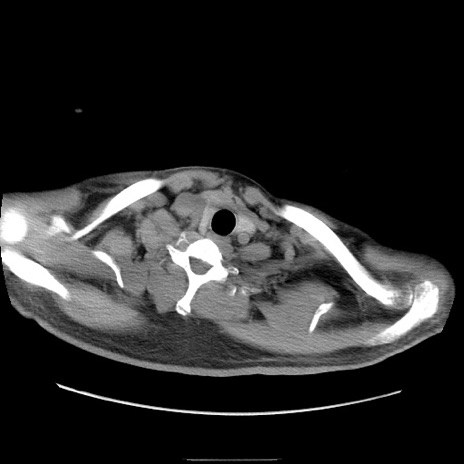

冠状断像